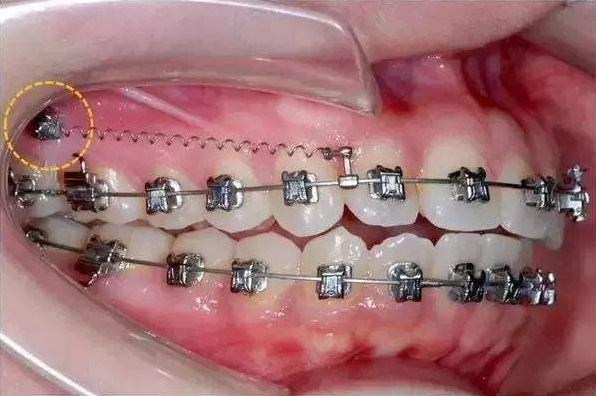

骨釘,顧名思義,是一種外形十分像釘子的種植釘,是放置在牙骨上方一個迷你的"釘子"。

它體積的小,好植入,近年來,逐漸成為正畸科常用的正畸輔助工具。

可不要看它體積小,卻在多種正畸方案中,成為醫(yī)生的得力助手,扮演著至關(guān)重要的角色

但是有了骨釘植入,就可以解決前者調(diào)節(jié)方案的煩惱,可以根據(jù)不同的調(diào)節(jié)方案,不同的調(diào)節(jié)需求,在口腔中相應(yīng)的位置植入骨釘形成口腔中的一個受力點,同時利用正畸器,橡皮筋相互拉力的作用下,更好的幫助醫(yī)生更好的控制牙齒的移動,做到"該移動的牙移動,不該動的牙不動"從達到佳的調(diào)節(jié)果。